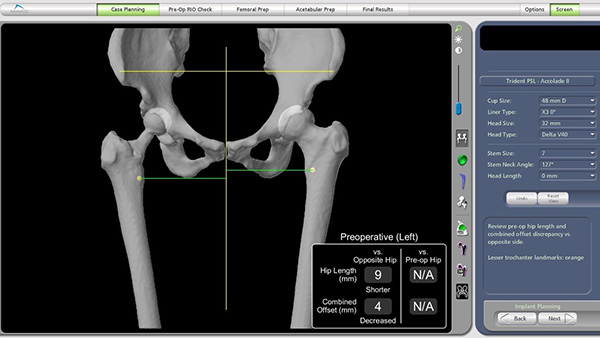

全髋关节置换手术患者最容易出现不满意的表现就是术后双侧下肢不等长,机器人关节置换术通过精准规划可以很大程度上避免这一并发症的出现,而术前规划离不开CT薄层扫描及三维重组技术。为此,放射科副主任燕飞牵头协调,制定了详细的扫描规范。技师长张永县带领技师朱蕾等完成了患者的术前下肢CT扫描,骨科团队基于患者CT影像资料进行三维建模和个体化术前规划,精确确定假体型号、髋臼杯角度和下肢力线,以确保术后肢体长度与功能恢复的最佳匹配。

术前影像显示右髋置换术后状态,左侧肢体较右侧短缩9mm。